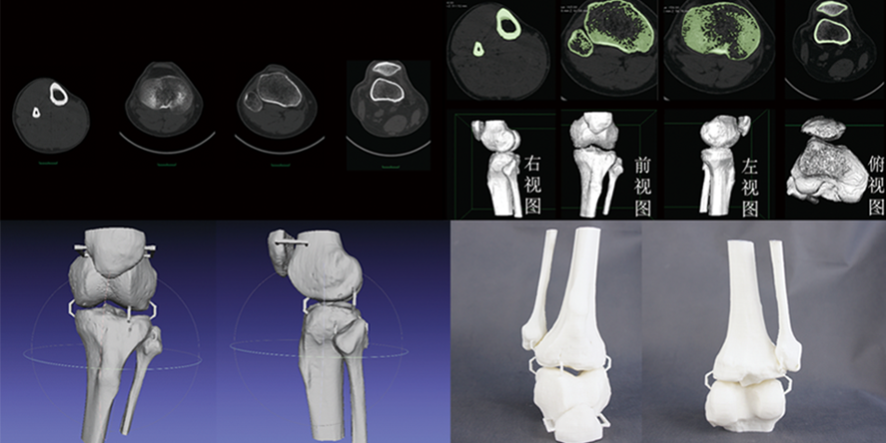

随着医学技术的飞速发展,3D打印骨骼和CT数据三维建模技术逐渐应用于骨科手术中,为骨科手术医生提供了新的解决方案。本文将介绍这些技术如何帮助医生提高手术准确性、降低手术风险和缩短康复周期,以及如何获取相关学习资源和培训途径。

3D打印骨骼和CT数据三维建模技术能够生成精确的患者解剖结构模型,帮助医生更清晰地了解骨折或畸形的详细情况。在手术前,医生可以利用这些模型制定个性化的手术方案,确保手术过程中的精确操作。

通过手术前的模拟和手术计划制定,医生可以提前预演各种可能的手术步骤和方案,从而降低手术过程中的不确定性和风险。此外,3D打印的患者特定导板和植入物也有助于提高手术安全性。